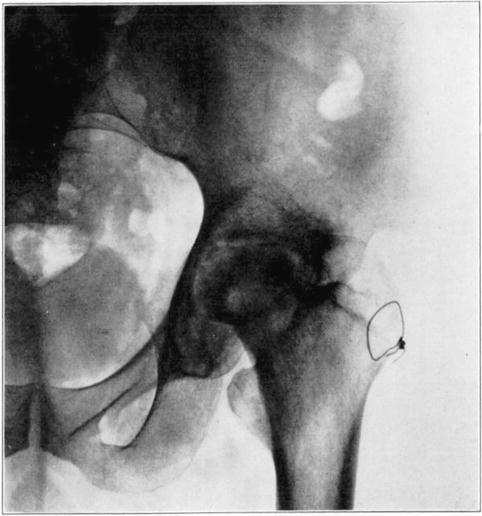

Operations which involve severence of bone or extensive separation of soft parts from bone may occasionally interfere with blood supply sufficiently to cause massive necrosis. An example of this is the necrosis of the head and neck of the femur in the following case in which arthroplasty of the hip was performed.

Case 1. Bony ankylosis following pyogenic arthritis.

Case 1. Twenty days after arthroplasty.

Case 1. Thirty-six days after arthroplasty. Beginning reduction in density in base of neck and shaft. No change in head.

Case 1. One hundred and fifty-one days after operation. Density of necrotic head unchanged but shaft and pelvis show atrophy of disuse.

Case 1. Two hundred and fifty days after operation. Head extensively reduced in density from invasion and replacement from the living bone of base of neck.

Case 1. Four hundred and four days postoperative Cavitation at base of head and further transformation.

The hip showed about forty degrees of flexion but marked limitation of abduction and rotation. Its strength had gradually improved and there was only slight discomfort in walking unless it was prolonged.

The cause for this exceptional occurrence of necrosis of head and neck without sequestration appeared to lie in the traumatism of head and denudation of neck of its covering of soft parts. However, it may have been due in part to deep-seated mild infection in the region of the new joint, despite the absence of discharge from that region. Failure of the necrotic head to be sequestrated speaks decidedly in favor of aseptic instead of septic necrosis although sequestration may not occur in the presence of mild infection of a necrotic area. In another case I observed necrosis of the head and neck following an arthroplasty in which there was infection of the wound with a purulent discharge, but the dead bone was sequestrated in the course of several weeks. In the case here reported functional stimulation of the bones resulting from movement of the joint, combined with protection of the necrotic head from weight-bearing, was followed by creeping substitution of the necrotic bone by new bone in the greater part of the head without either erosion of dead bone or the development of marked deformity.

Death of the proximal fragment predisposes to non-union, but union occurs in a considerable percentage of the cases with a dead head in which there is impaction of fragments or in which there is efficient reduction and fixation of fragments, the best results apparently being obtained from the closed abduction method of Whitman. At the end of the period of immobilization the distal living fragment usually shows roentgen-ray signs of reduced density due to atrophy of disuse, but the necrotic head which cannot atrophy casts practically as even and heavy a shadow as at the time of fracture. This usually makes it possible to diagnose necrosis roentgenologically at this stage.

If bony union occurs the head is gradually invaded by the ingrowth of tissue from the distal fragment and sometimes from the hypertrophied round ligament. The necrotic marrow is replaced by vascular connective tissue and eventually by bone marrow, but the necrotic bone is much more slowly absorbed and replaced by a variable amount of irregularly arranged living bone. The necrotic cartilage is slowly absorbed and replaced by fibrous tissue, fibro-cartilage, and to some extent eventually by new hyaline cartilage. If too much weight is borne on the head before it has been transformed into new bone, its weight-bearing portion may collapse with a resultant deformity and a poor functional result, but this may be averted by prolonged avoidance of weight-bearing. The functional stimulation which comes from motion of the limb without weight-bearing is sufficient to hasten transformation of the head.

Necrotic femoral head casting heavier shadow than surrounding atrophied living bone.

Roentgenogram of slice of excised head in Fig. 7, showing old necrotic bony trabeculae still undisturbed.